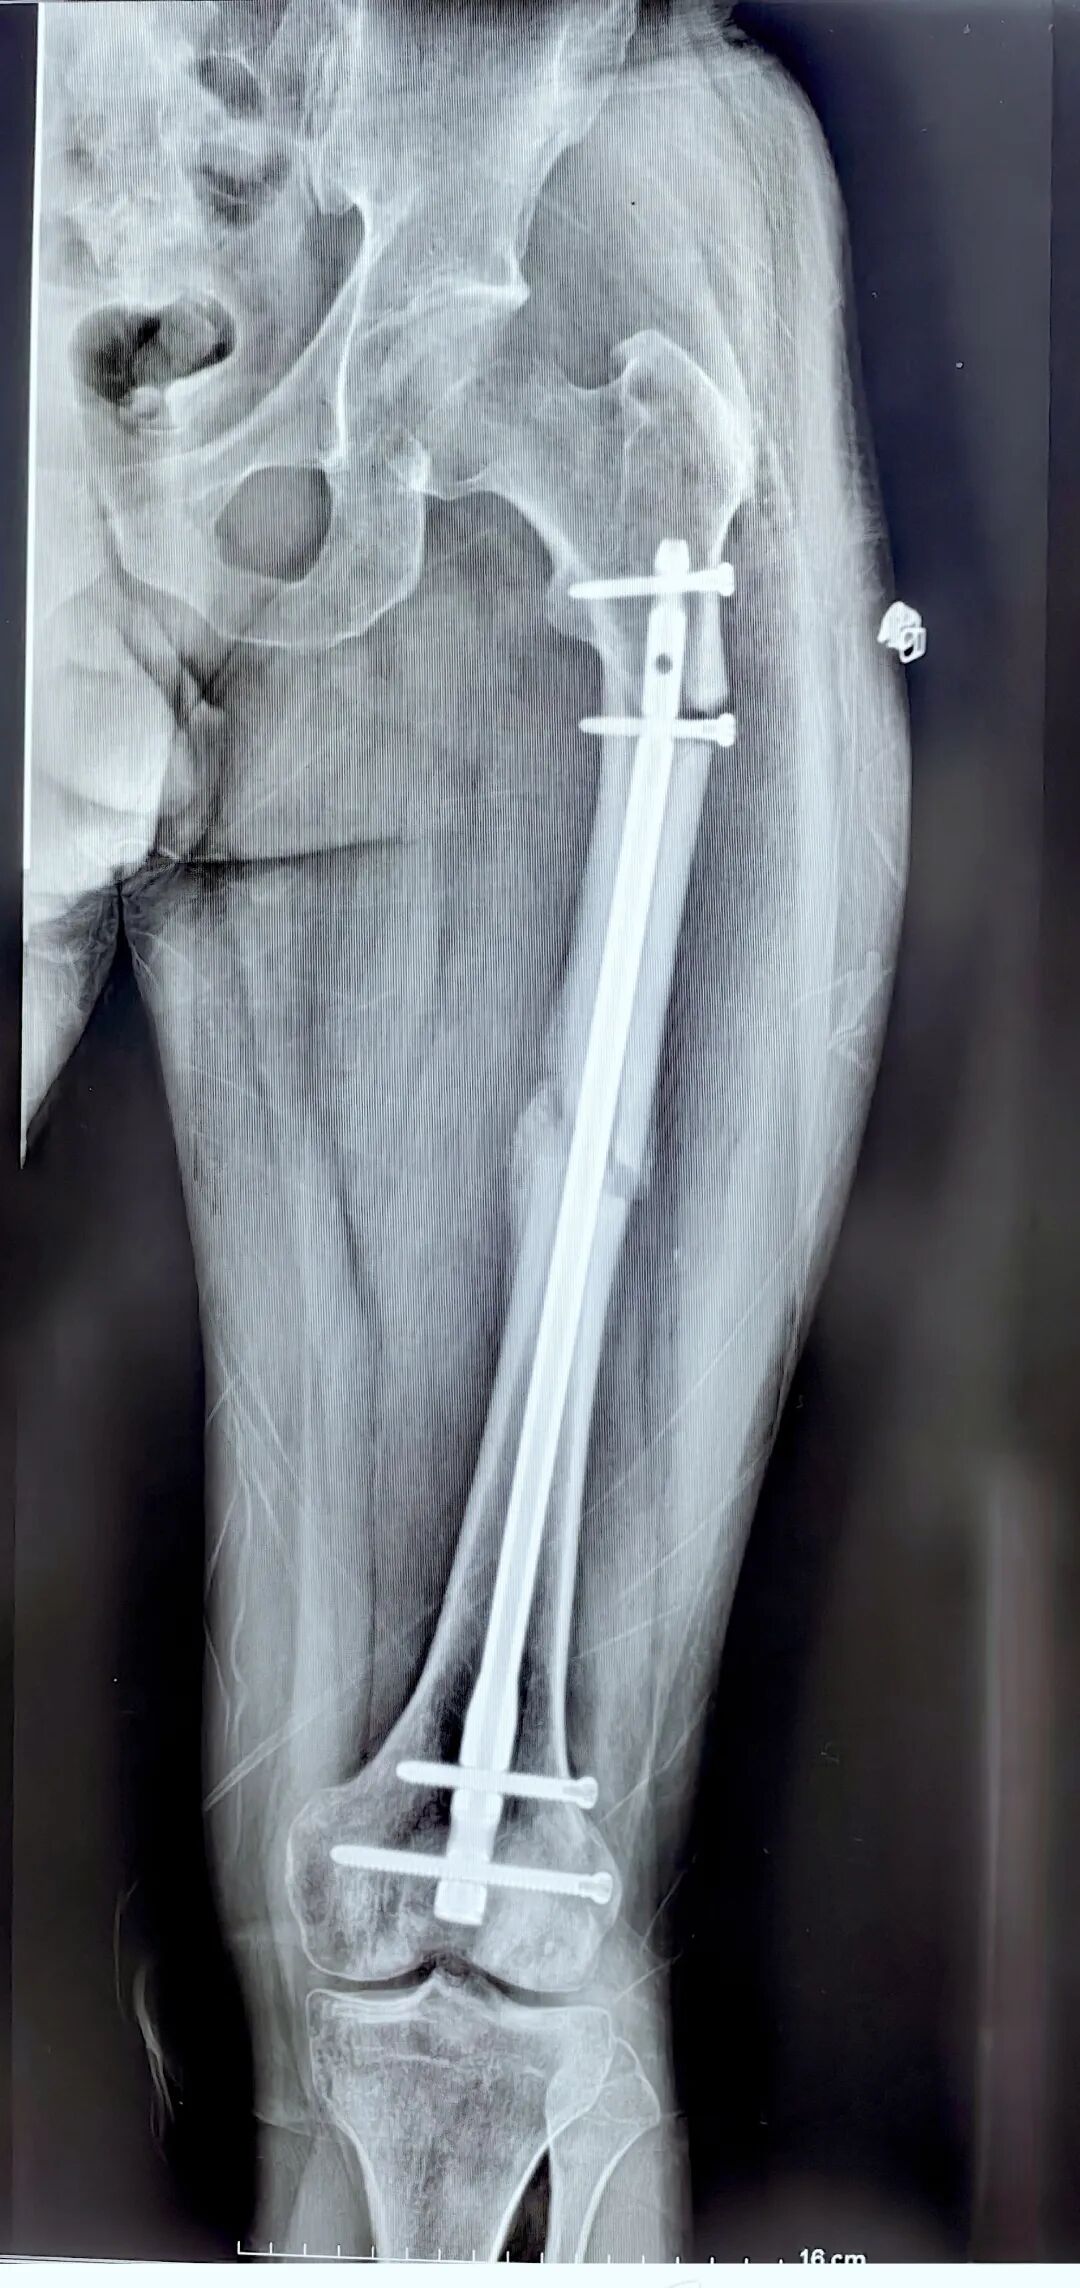

青年男性,股骨干骨折,切开复位,逆行髓内钉

逆行髓内钉:距膝关节间隙20 cm以内的骨干骨折、股骨髁上及髁间骨折。

术后3个月,弃拐负重,正常上班